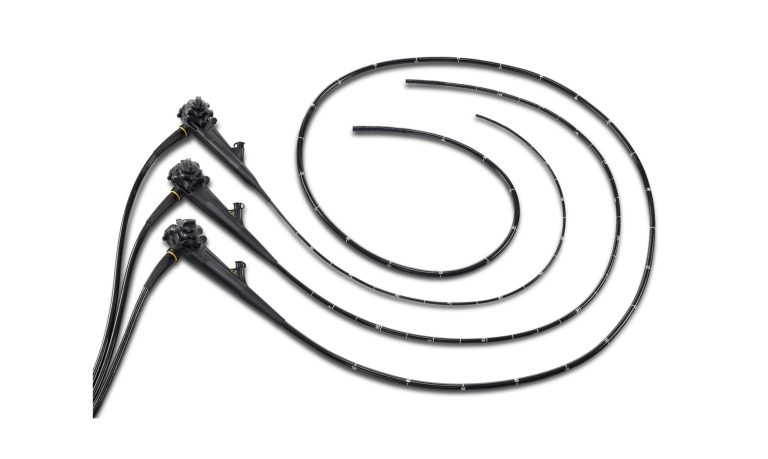

EndoScope

V-2000 Veterinary Endoscopy

Benefiting from more than 20 years of technological know how, V-2000 is designed for frontline veterinarians. This versatile full high definition video system center that is compatible with flexible, rigid and fiber endoscopes, therefore encompassing a large array of animal care needs.

V series flexible endoscopes

An upgraded scope tubing with a light weight handle, the V series scopes offer great comfort and ease during routine and complex operations, helping to shorten the procedure time.

A shorter bending radius coupled with a large field of view allows you to intubate and reach efficiently, and to observe to the full extent. Diagnose and treat with confidence, thanks to the scope’s water jet function and large instrument channel.

One Step connection, and real waterproof, the V series scopes can be plugged and unplugged, cleaned and disinfected straightforwardly, at only a minimal risk of water damage by mismanipulation.